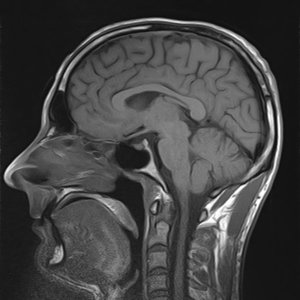

Są takie sytuacje w życiu, gdy podejrzenie urazów wewnątrz ciała wymaga diagnozy za sprawą obrazowania metodą rezonansu magnetycznego, tzw. MRI. Jest ono szczególnie przydatne wtedy, gdy musimy zaobserwować zmiany chorobowe w tkankach zasłoniętych kośćmi, czyli np. mózgu, serca, czy niektórych mięśniach. Możemy również poddać się obrazowaniu w celach naukowych, np. podczas badań statystycznych. MRI jest nieinwazyjną techniką diagnozy, lecz ze względu na działanie bardzo silnego pola magnetycznego, a także na specyficzny sposób badania, musimy się do niego zawczasu przygotować. O czym należy pamiętać?